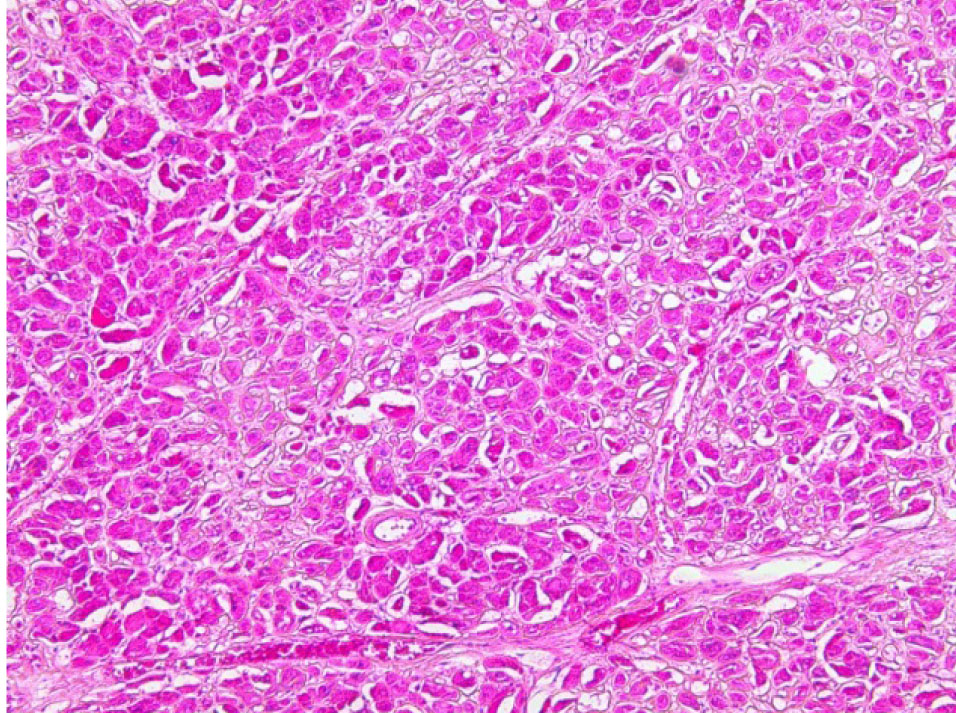

Почки – резкое уменьшение числа клубочков, отдельные полностью замещены однородной массой, дающей положительную реакцию на амилоид (рис. 3). В стенке сосудов также видны отложения амилоида (рис. 4).

Рис. 3. Почечный клубочек замещен амилоидными массами. Окраска конго красный, ×400